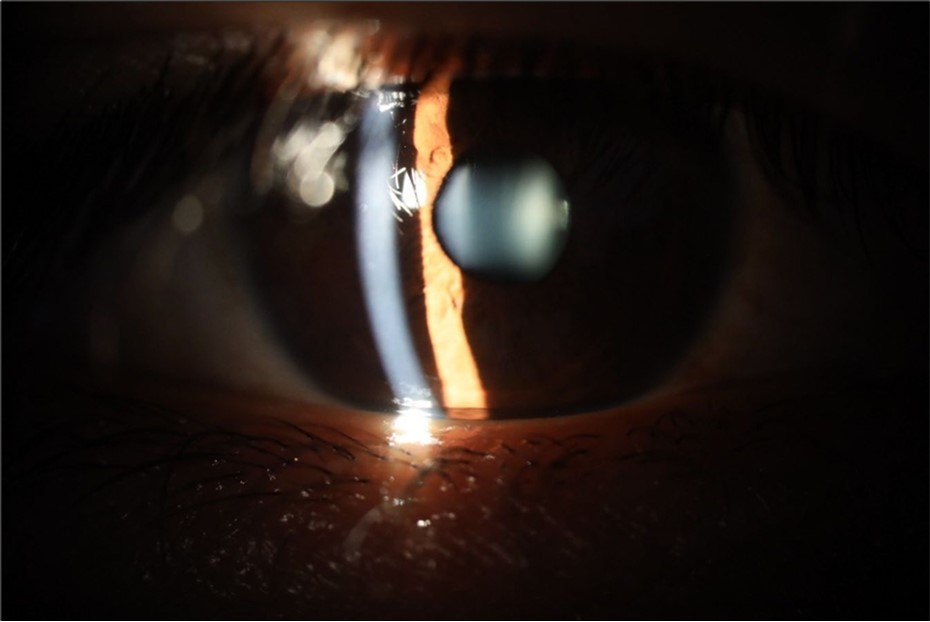

Figure 15.The photograph shows better specular reflection, compared to the first day of the exam.

Figure 16.The anterior segment of the right eye shows the vitreous with greater transparency. The cornea and lens, as well as the anterior chamber, are in good condition.